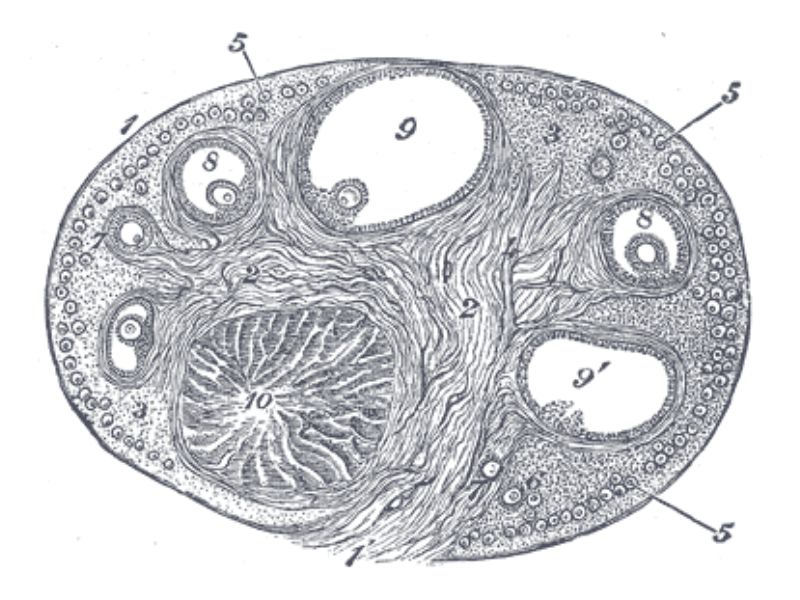

Section of the ovary

1. Outer covering. 1'. Attached border. 2. Central stroma. 3. Peripheral stroma. 4. Bloodvessels. 5. Vesicular follicles in their earliest stage. 6, 7, 8. More advanced follicles. 9. An almost mature follicle. 9'. Follicle from which the ovum has escaped. 10. Corpus luteum.

Ovary

- Capsule covered by modification of peritoneum

- Called germinal epithelium

- Simple squamous/cuboidal

- Subdivided

- Not clearly defined

- Cortex - contains ovarian follicles

- Medulla - vascular

Germinal epithelium

- Misnomer

- NOT source of primary follicles

- Cover capsule

- Simple squamous/cuboidal epithelium

Cortex

- Tunica albuginea

- Irregular dense CT capsule

- Follicles in various phases

- Stroma containing follicles

Stroma

- Highly cellular loose CT

- Fibroblasts

- Elastic & collagen fibres

- Form layers around follicles

Medulla

- Blood vessels

- Hilus cells

- Stroma

Blood vessels

- Enter medulla at hilus

- Supply the cortex

- Epithelioid cells clump around blood vessels

Epithelioid cells

- Located in hilus

- Also called hilus cells

- Clump around blood vessels

- ≈ Leydig cells

- Probably produces androgens